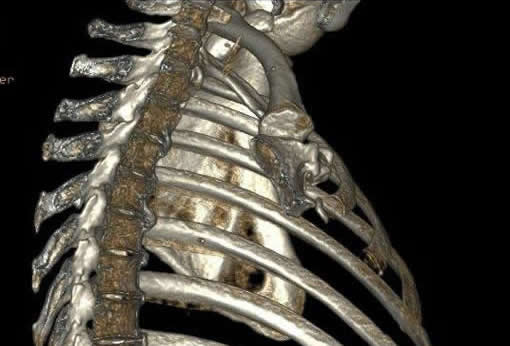

当院では64列CTを導入し、従来のCT装置では難しかった心臓の検査をはじめ、データを3次元的に収集するため、あらゆる方向の画像を再構成でき、3D画像も作成できます。

64列になったことにより、速やかに、低被ばくで検査ができ、鮮明な画像を得ることができます。

肋骨3D